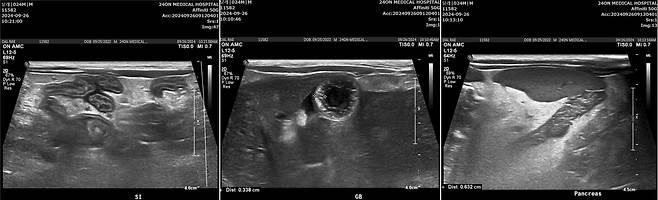

달래는 복부 초음파 검사에서 담낭과 총담관의 벽이 심하게 비후해지고, 소장 주위 림프절, 복막에도 염증 소견이 함께 관찰됐다. 염증성 장병증도 함께 의심되는 상황이었다. 다행히 췌장 쪽은 특이 소견이 발견되지 않았다.

그 결과 한 달 후 혈액 검사 시 간 수치가 정상화되고 복부 초음파 검사에서도 모든 증상이 개선돼 담관간염 치료를 종결할 수 있었다.